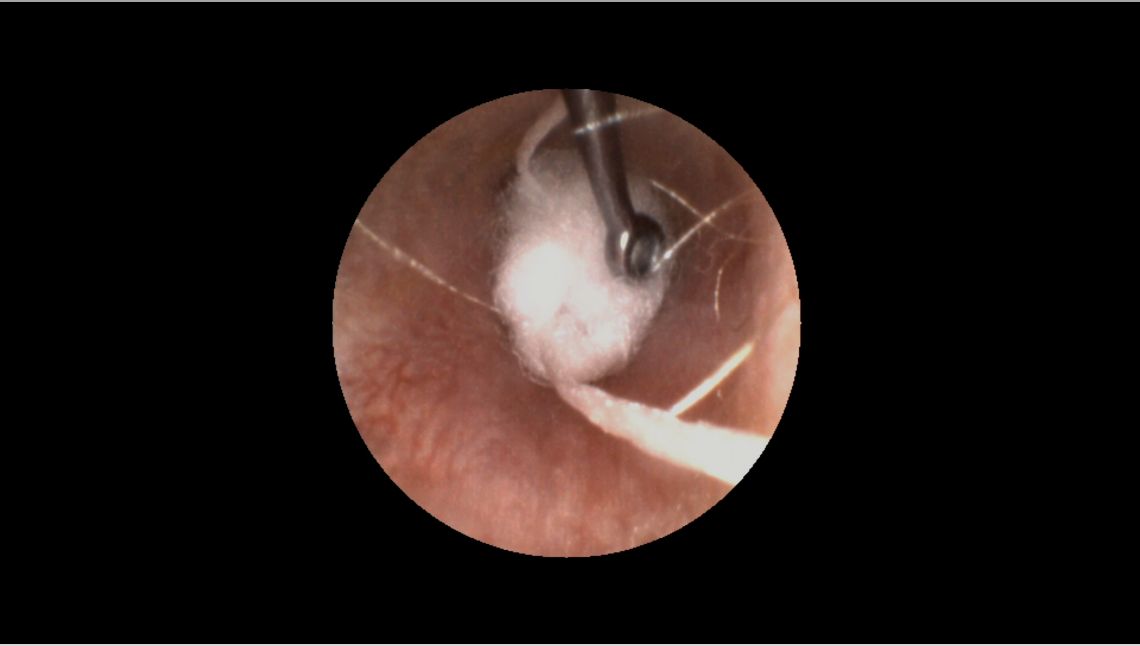

- 검이경과 팁을 사용하여 귓솜이 외이도의 두 번째 굴곡부를 지나도록 밀어 넣은 다음 고막에 최대한 가깝게 배치합니다.

- 빈 틈의 여부에 대해 검이경으로 귓솜의 주변부를 검사하여 작업 결과를 확인합니다.

전문가의 팁: 전문가의 자세를 낮춰 귀와 평행하게 하고 귓바퀴를 위로 올린 다음 이주를 앞으로 당기면 원하는 부위를 쉽게 볼 수 있습니다.